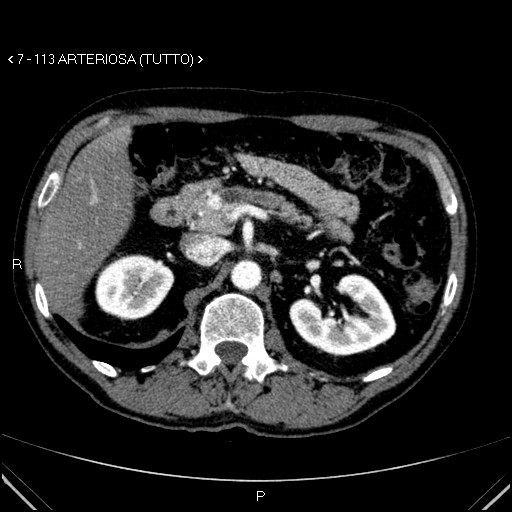

image

Aspetti TC: piccolo nodulo istmico iperdenso in fase venosa.